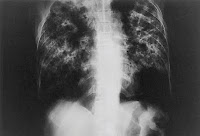

Na imagem: Esculápio, deus da Medicina da Mitologia greco-romana.